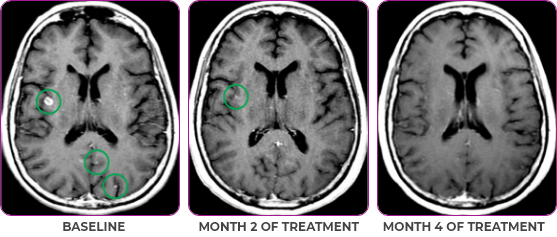

Response in primary and metastatic lesions1

MRIa imagery of the brain. Green circles indicate baseline brain metastases.1

SCAN 2: BRAIN

aMRI, magnetic resonance imaging.

Pre- and post-treatment imaging, by Rosen EY et al, is licensed under Creative Commons License CC BY 4.0.

- Partial response to treatment that was confirmed at 2 months (34% tumor reduction)

- Patient remains on VITRAKVI after more than 4 months of treatment